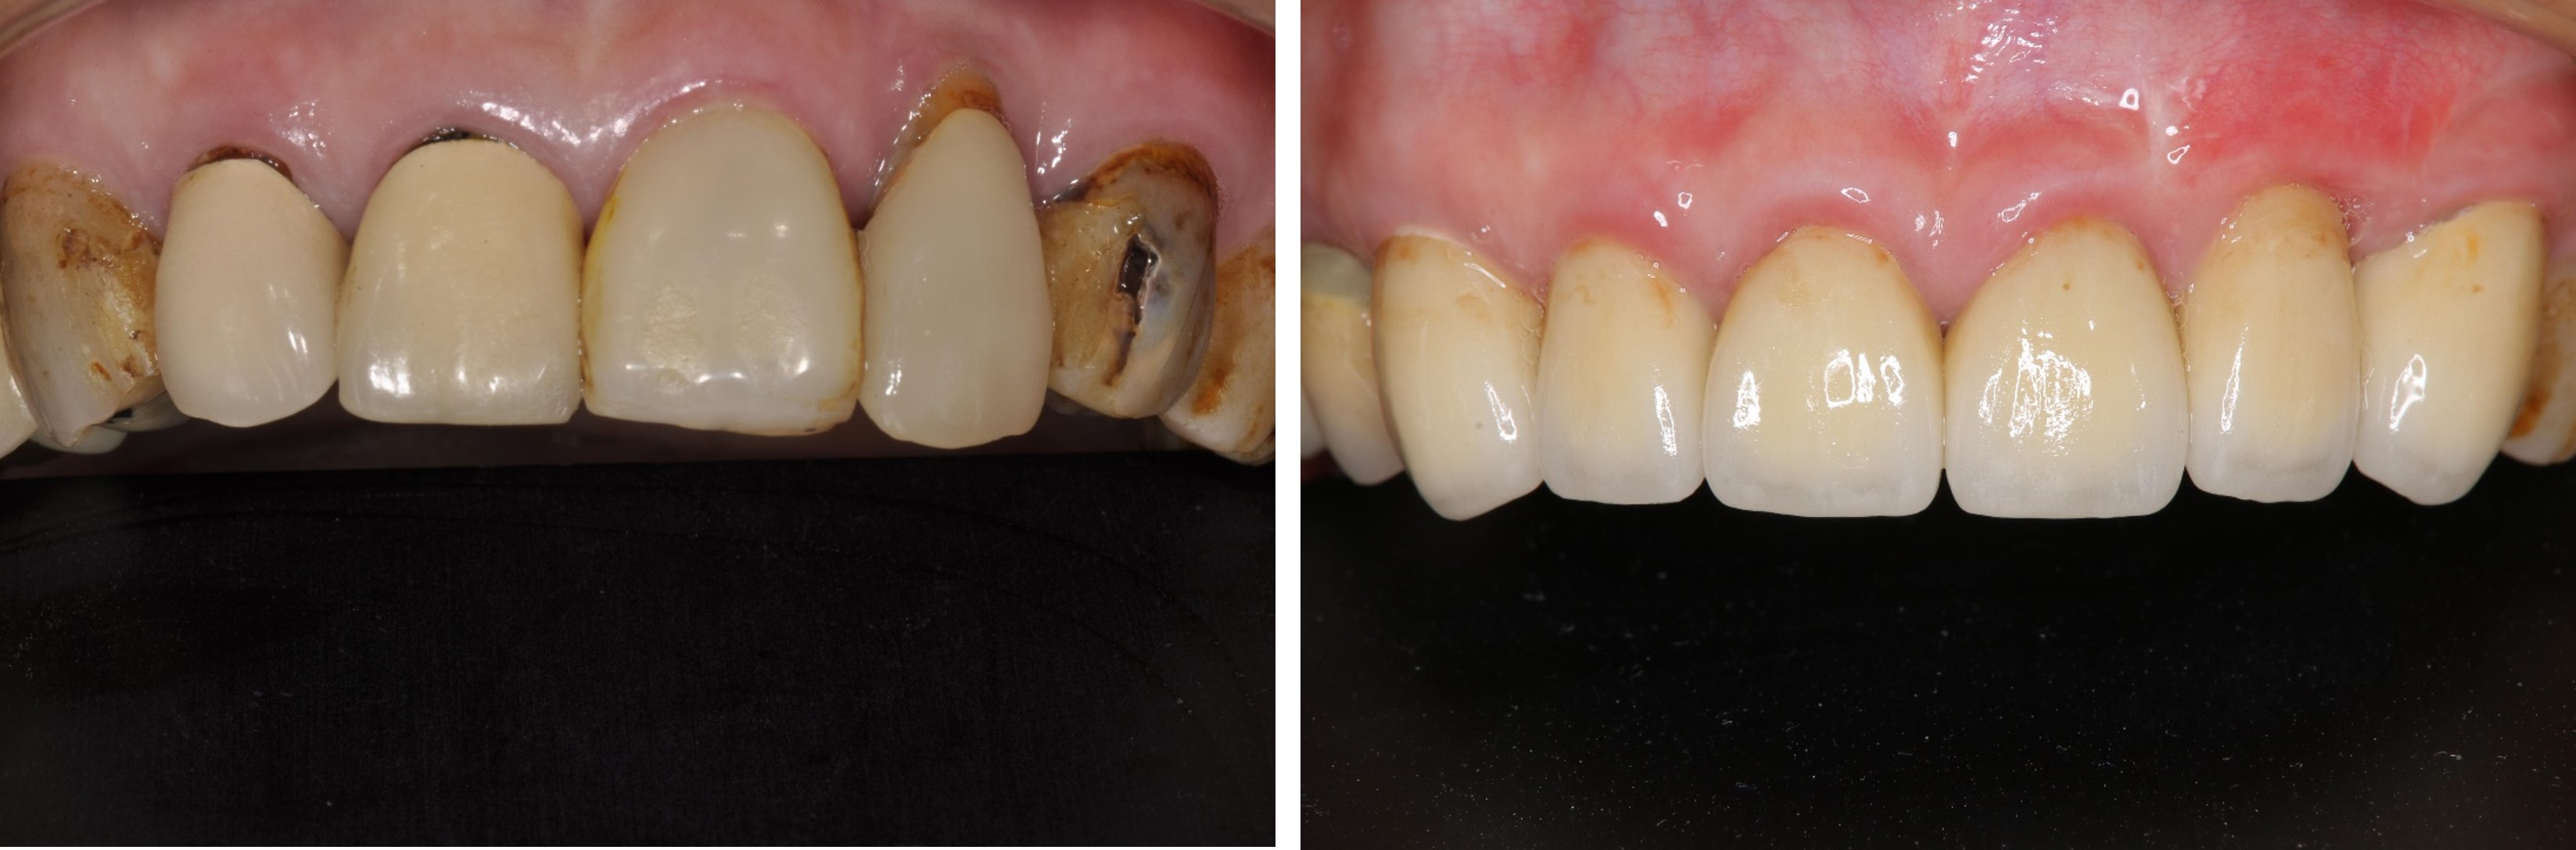

前牙及植牙全瓷冠

治療後,咬合牙周適應良好

治療後,密合度良好

術前、術後比較